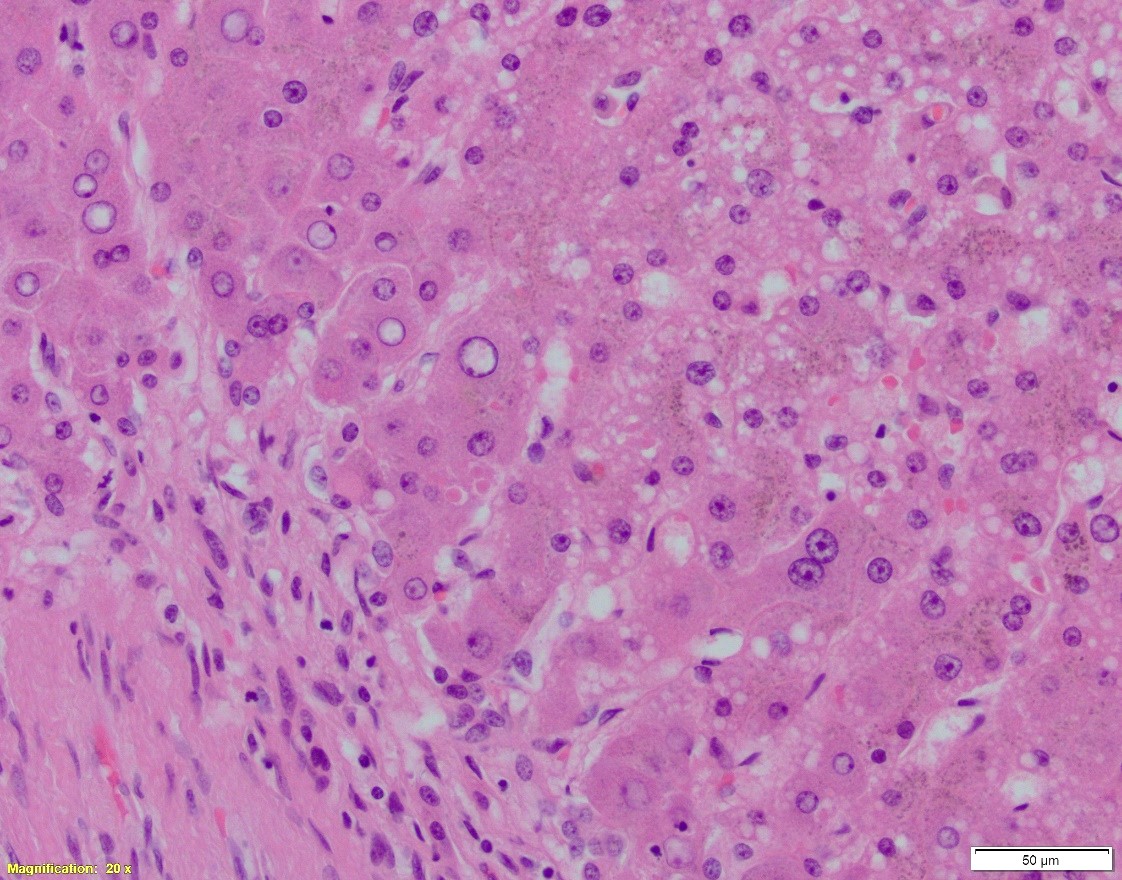

Patient is a 66-year-old female with NASH cirrhosis s/p OLT. Specimen: native liver explant. Pictures:

A. Hematoxylin and eosin, 20x. B. Hematoxylin and eosin, 100x. C. PAS w/diastase, 40x

In cirrhotic liver removed for transplantation, A1-antitrypsin deficiency grossly presents as micronodular or mixed micro- and macronodular pattern of cirrhosis. Microscopic findings include intracytoplasmic eosinophilic globules in periportal hepatocytes, which does not always correlate with the clinical liver disease. PAS w/diastase is helpful to distinguish A1-antitrypsin globules from glycogen. In infants, the globules may be absent or hard to detect; in these children, however, the disease may present as liver injury in form of neonatal hepatitis, cholestatic hepatitis, or extrahepatic biliary atresia, with variable degrees of fibrosis. In adults, besides the presence of A1AT globules, the changes may include mild portal inflammation and bile ductular proliferation, mild steatosis, and variable fibrosis.

Other eosinophilic inclusions that can mimic A1AT deficiency on H&E are mega-mitochondria, macrophages containing granules, immunoglobulin and fibrinogen (afibrinogenemia) globules, and rarely, lipofuscin.